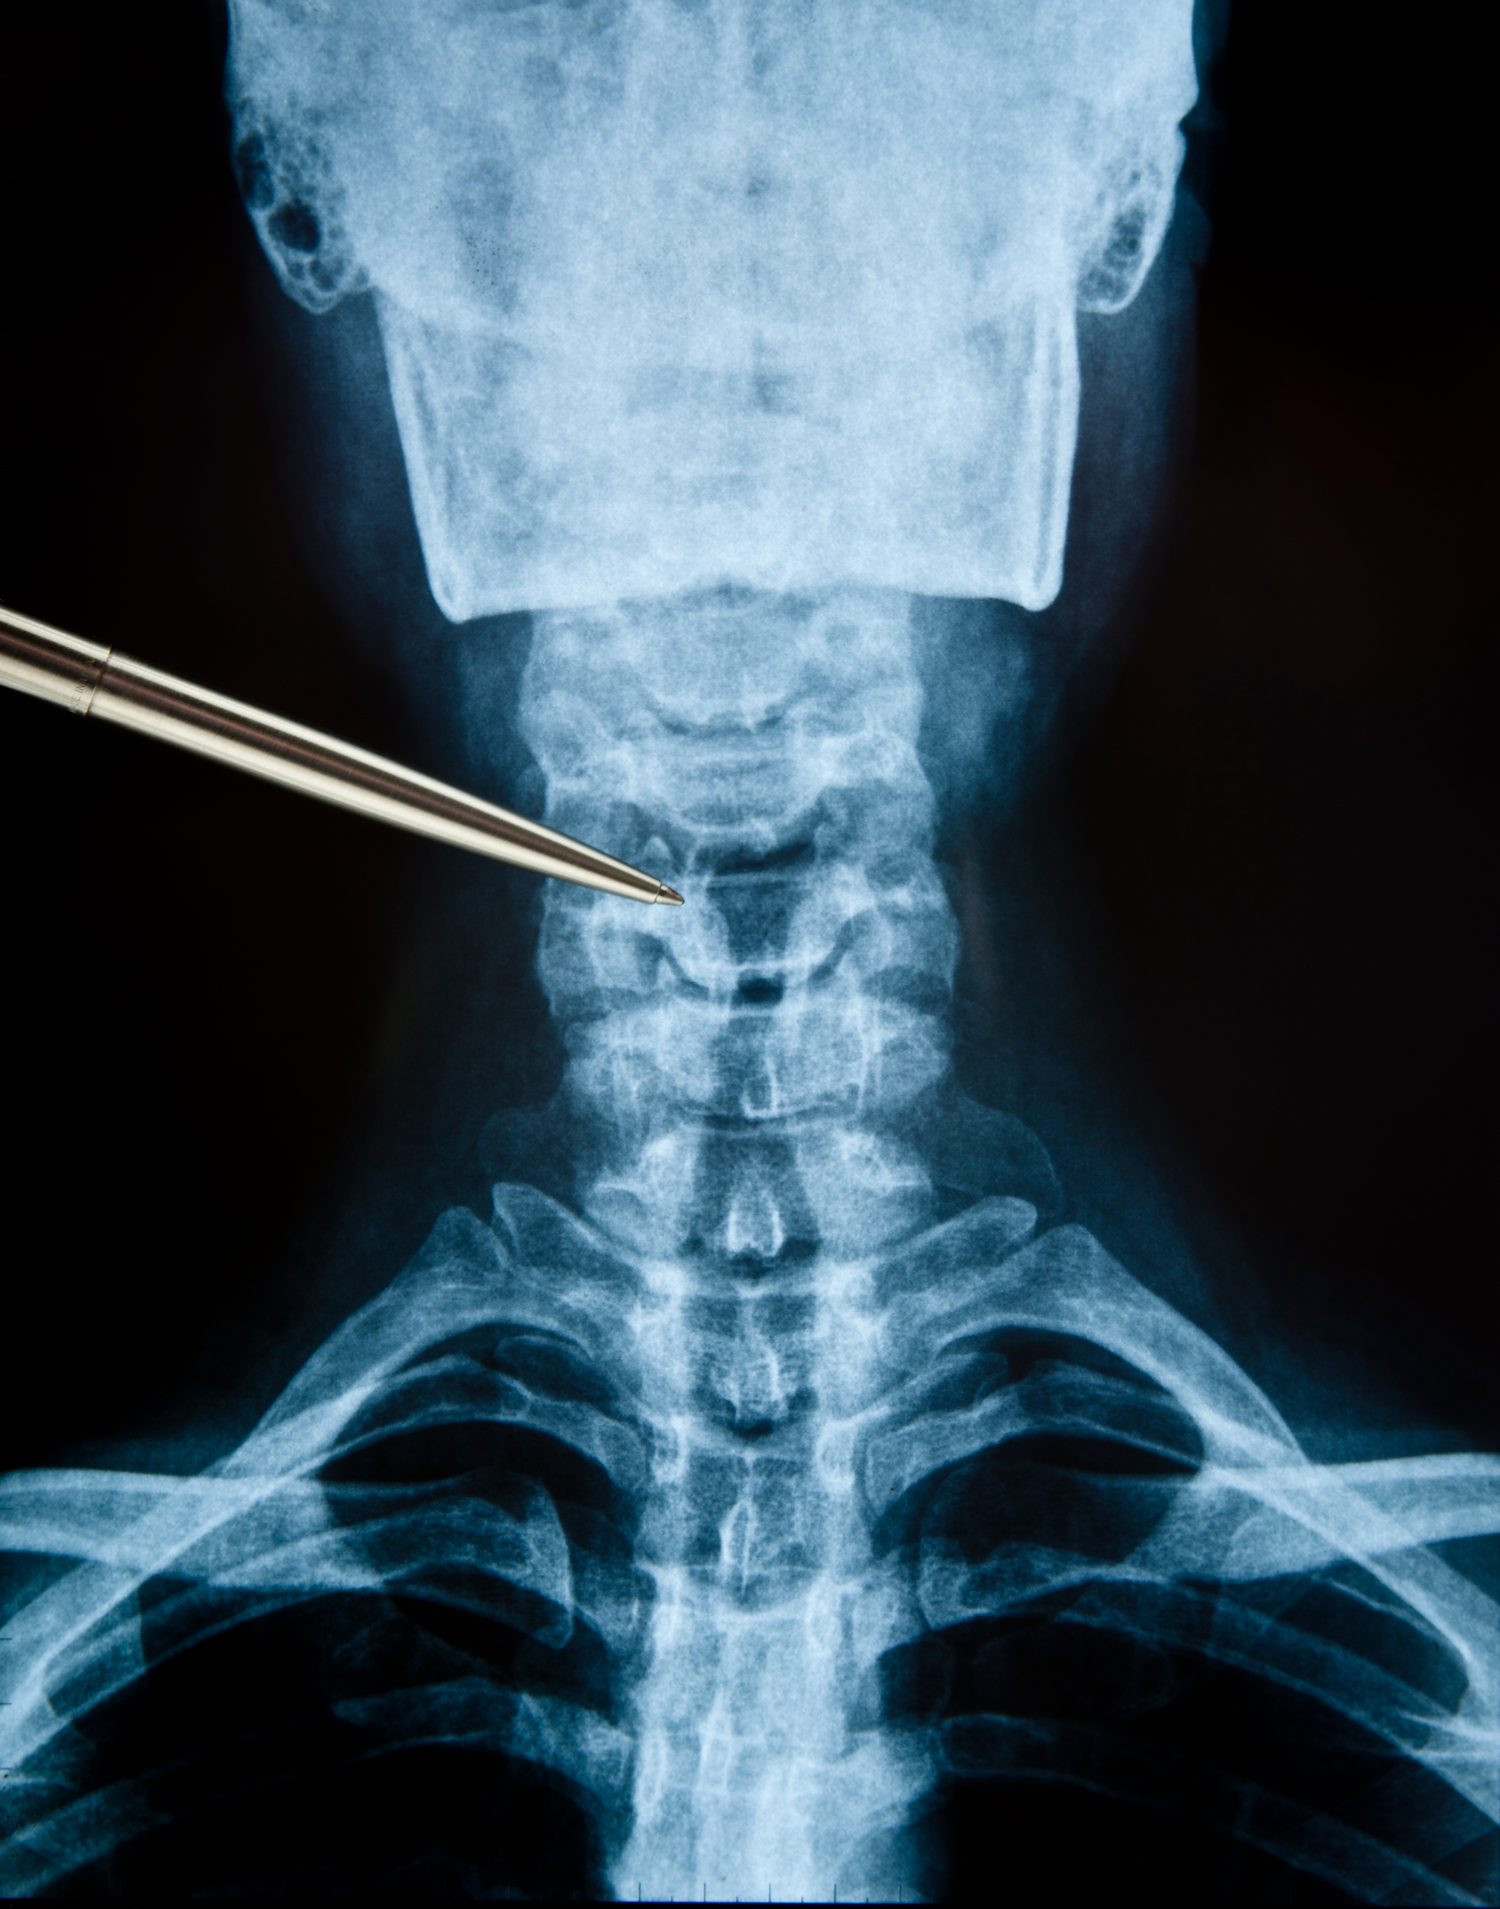

1.1 Operationen an der Halswirbelsäule (HWS)

Ein Bandscheibenvorfall der Halswirbelsäule kann zu Schmerzen, Taubheitsgefühlen oder Kraftverlust im Arm oder in der Hand führen. Wenn diese Beschwerden trotz konservativer Behandlung bestehen, kann eine Operation notwendig sein.

Ziel der Operation (HWS)

Druckentlastung der betroffenen Nervenwurzel oder des Rückenmarks.

Operatives Vorgehen (ventrale Diskektomie und Fusion)

Der Eingriff erfolgt in der Regel von vorne über den Hals (ventraler Zugang).

Die betroffene Bandscheibe wird vollständig entfernt. Anschließend wird der Zwischenraum mit einem kleinen Implantat (Platzhalter aus Kunststoff oder Titan) stabilisiert. In einigen Fällen wird zusätzlich eine kleine Platte implantiert, um die Stabilität zu verbessern.